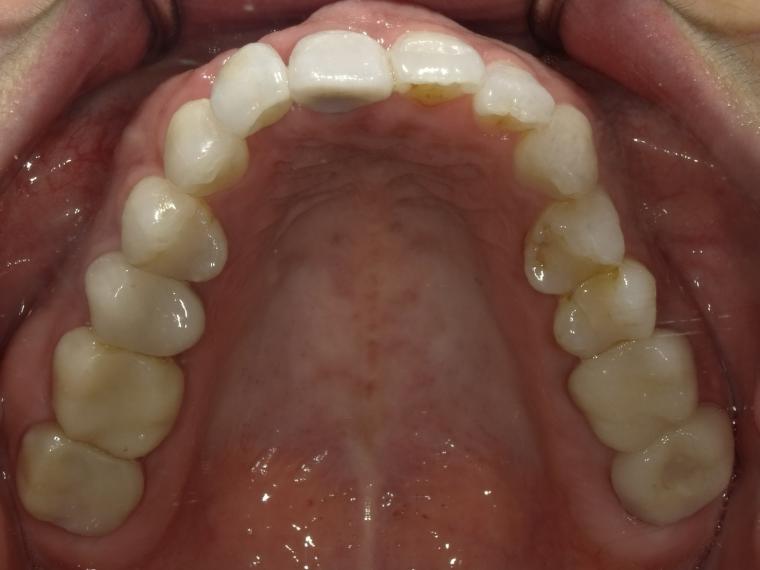

AFTER

53歳女性/上1本欠損/インプラント埋込手術

抜歯後に土台となる骨を作る処置の後、インプラントを1本埋入しました。

現在も定期健診で拝見しております。